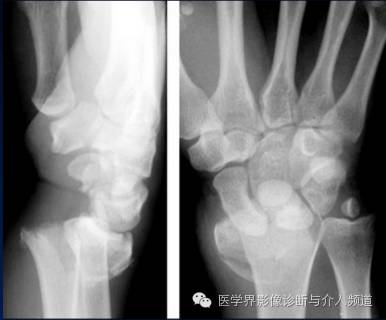

3、Bennett’s骨折

第一掌骨基底部骨折。为关节腔内骨折,非粉碎性,骨折线累及第一掌腕关节面。第1掌骨则由于拇长展肌的牵拉,导致向桡侧和背侧脱位,近端基底部骨块呈四边形。

4、Rolando 骨折

第一掌骨基底部粉碎性骨折并脱位。为关节囊内骨折,需要与Bennett’s骨折鉴别,Bennett’s骨折为非粉碎性骨折,Rolando 骨折有3个以上的骨碎块。